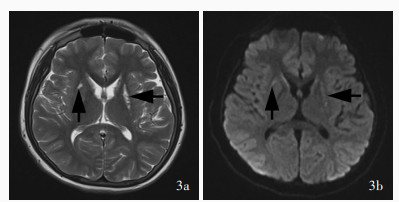

Ji K , Wang W , Lin Y , Xu X , Liu F , Wang D , Zhao Y , Yan C . Mitochondrial encephalopathy due to a novel pathogenic mitochondrial tRNA Gln m. 4349C > T variant. Ann Clin Transl Neurol, 2020, 7: 980- 991.